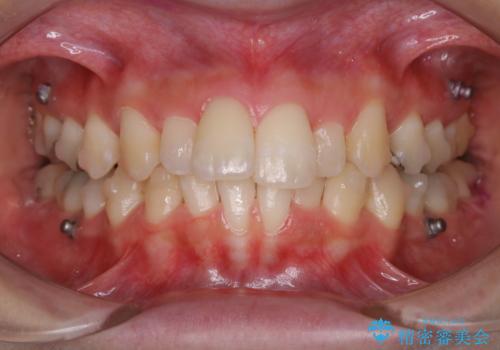

- インビザラインで矯正治療中にクリーニングを希望されました。PMTC60分コースで、クリーニングと歯ブラシ指導を行いました。

磨けているようでも、染出しをして目に見えるプラーク(歯垢)を確認することで、より正しいブラッシング方法を身につけることができます。インビザライン中は、歯にアタッチメントをつけるため、歯の表面がデコボコしてプラークが付きやすい状態になります。毎日のケアでしっかりと汚れを落として虫歯や歯周病・口臭のリスクを減らしていくことが大切です。定期的にメンテナンスを行い、ケアがどれくらい出来ているか確認したり歯科医院で専門的な機械や器具によるPMTCを行うことをおススメします。